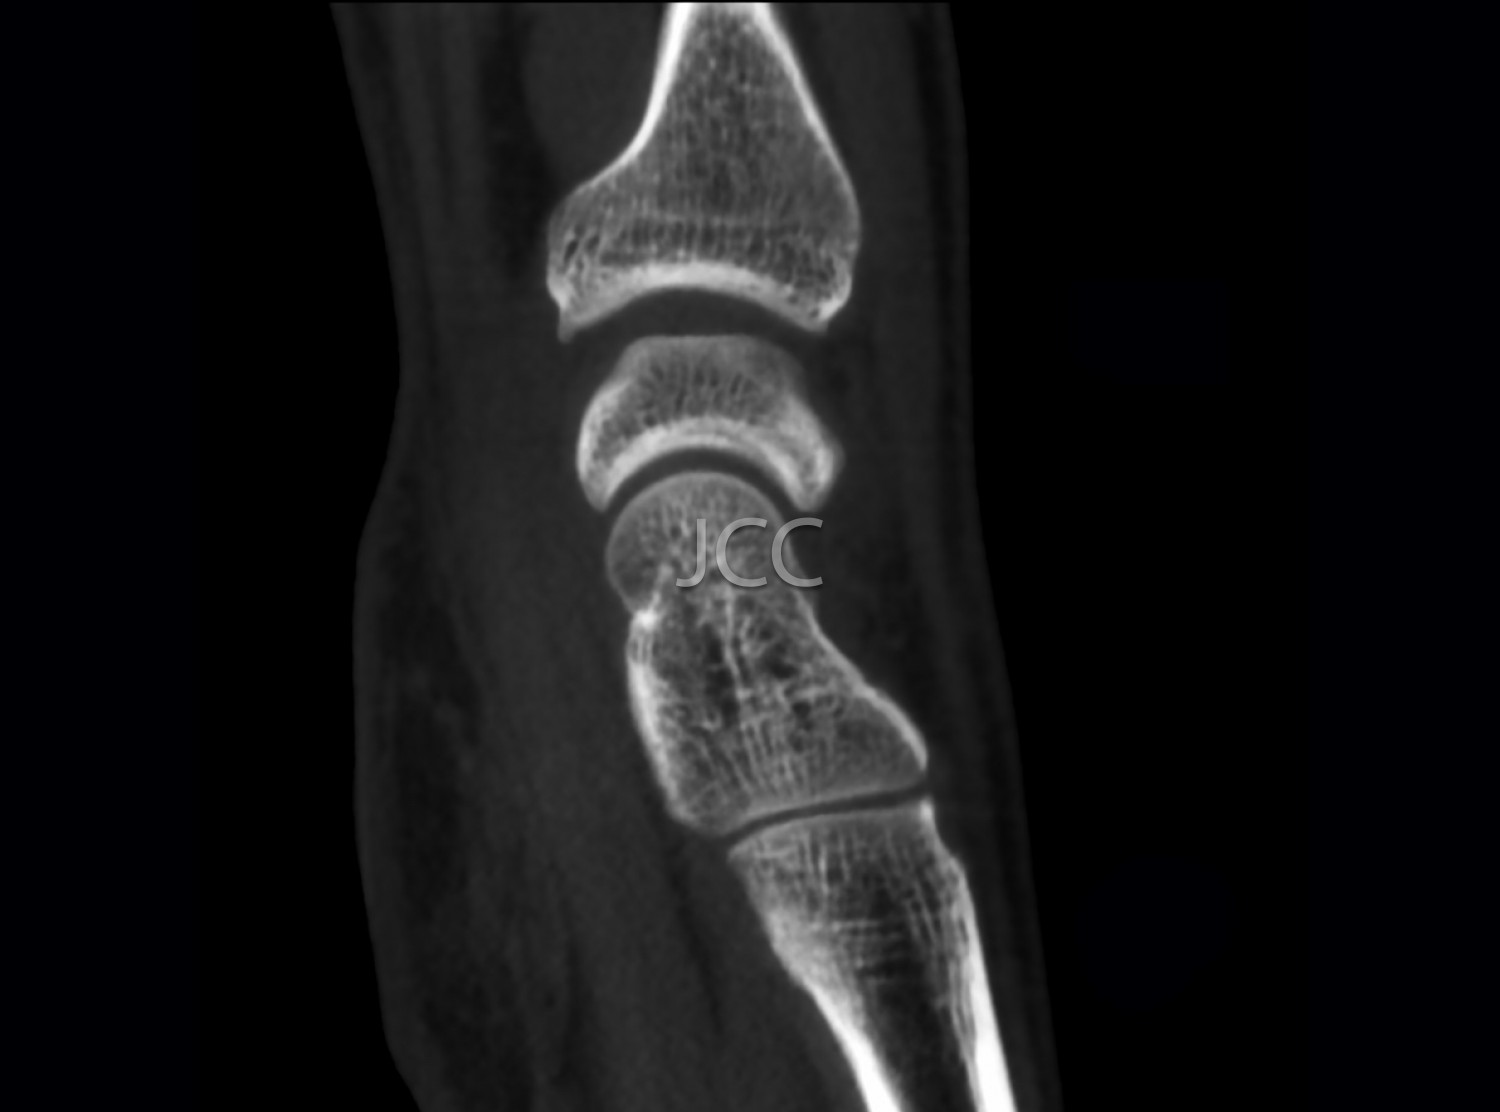

Cone Beam CT - Small Joints - Wrist / Hand / Fingers CBCT

We use a CBCT equipment which allows the study in low-dose radiation and very high spatial resolution of the bone structures of small joints, such as joints of the wrist, elbow, hands, feet, fingers, etc.

Taking into account the superior spatial resolution of the CBCT for bone evaluation compared to state of the art multi-cut CT equipment, this modality actually allows detecting small fractures or discrete small bone changes more effectively than the CT.